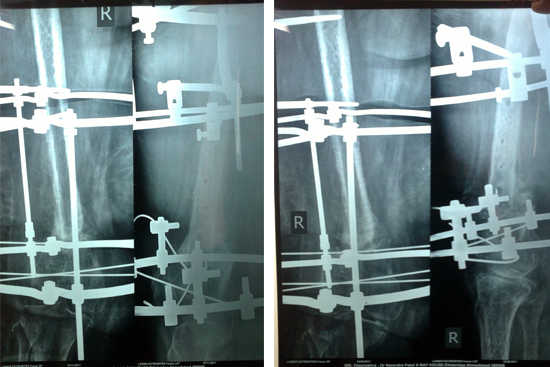

Non Union Femur

Case 1

Case 2 (Rampyari)